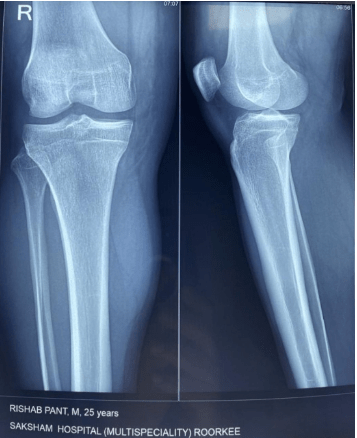

ಆಸ್ಪತ್ರೆಯಲ್ಲಿ ಪಂತ್ ತಾಯಿಯೂ ಇದ್ದಾರೆ: ರಿಷಬ್ ಪಂತ್ ಅವರನ್ನು ಡೆಹ್ರಾಡೂನ್ನ ಮ್ಯಾಕ್ಸ್ ಆಸ್ಪತ್ರೆಗೆ ದಾಖಲಿಸಲಾಗಿದೆ, ಅಲ್ಲಿ ಅವರ ತಾಯಿ ಕೂಡ ಅವರೊಂದಿಗೆ ಇದ್ದಾರೆ. ಪಂತ್ ತಲೆ ಮತ್ತು ಮೊಣಕಾಲುಗೆ ತೀವ್ರ ಗಾಯಗಳಾಗಿವೆ. ಅವರ ಎಂಆರ್ಐ ಕೂಡ ಮಾಡಲಾಗಿದೆ. ಇದಲ್ಲದೆ, ಬೆನ್ನು ಮತ್ತು ಕಾಲುಗಳ ಕೆಲವು ಭಾಗಗಳು ಗಾಯಗೊಂಡಿವೆ. ಶುಕ್ರವಾರ ಬೆಳಗ್ಗೆ 5.30ಕ್ಕೆ ರೂರ್ಕಿ ಬಳಿಯ ಮೊಹಮ್ಮದ್ಪುರ ಜಟ್ ಪ್ರದೇಶದಲ್ಲಿ ಪಂತ್ ಅಪ#ಘಾತ ಸಂಭವಿಸಿದೆ. ಇವರು ಆದಷ್ಟು ಬೇಗ ಗುಣಮುಖರಾಗಲಿ ಎಂದು ಆ ದೇವರಲ್ಲಿ ಬೇಡಿಕೊಳ್ಳೋಣ.